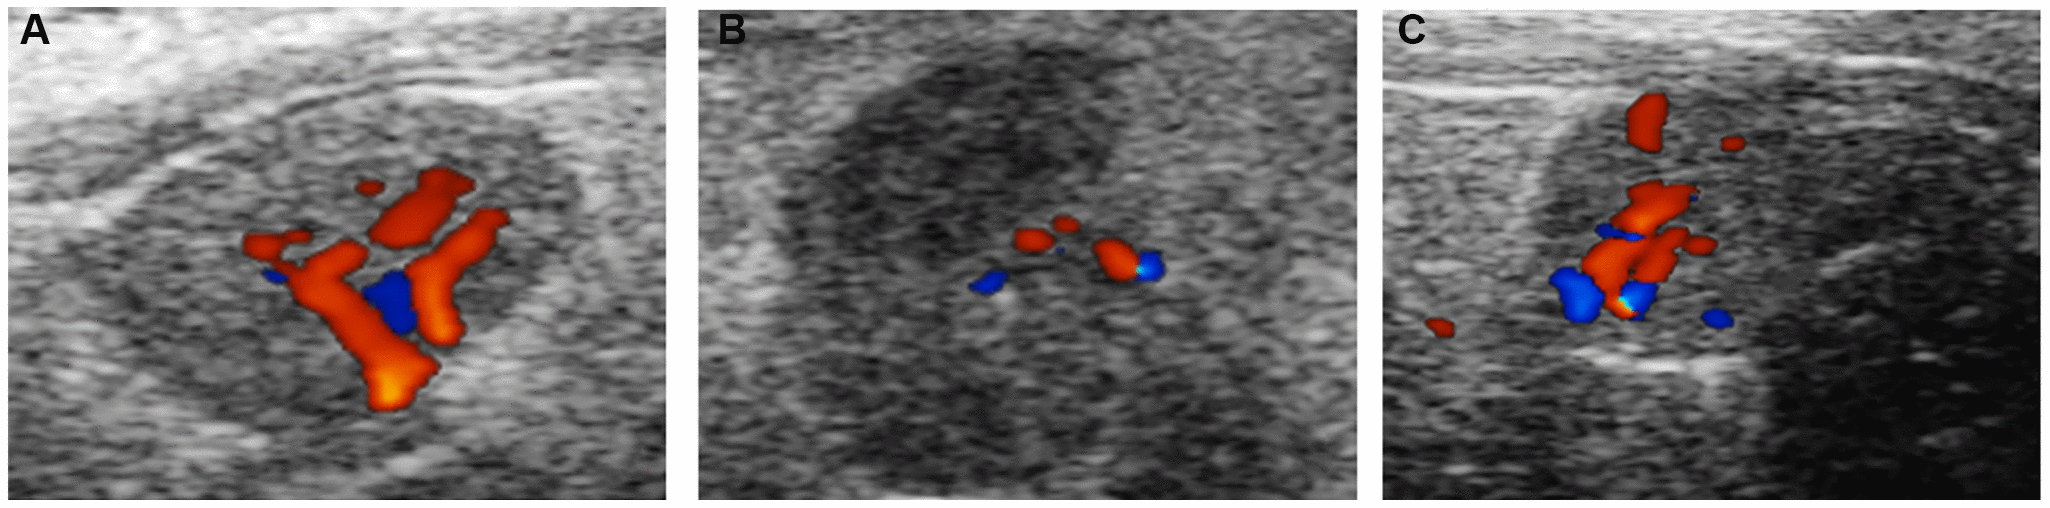

Figure 3. Ovarian blood flow under ultrasound. (A) Normal group; (B) Natural aging non-intervention group; (C) Natural aging intervention group.